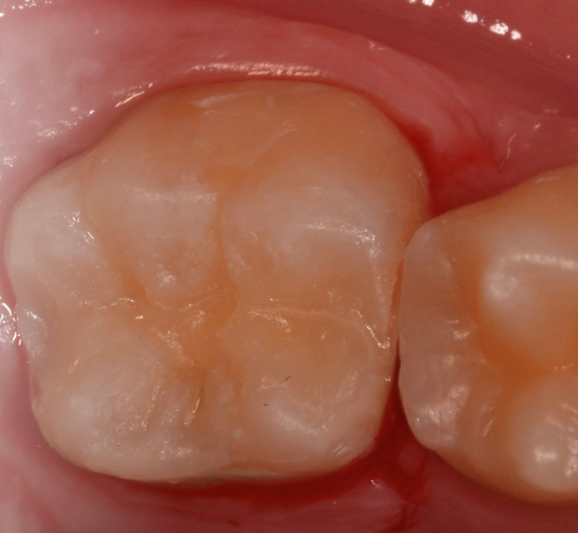

To create anatomy in occlusal surfaces, place a Teflon strip on the surface, press the stamp to place, and light cure (Fig. 6). The Teflon prevents the stamp from sticking to ACTIVA, and the bur shaft is the handle for placement and removal of the stamp. The immediate result duplicates the original surface anatomy (Fig. 7), and after removal of any flash, the ACTIVA restoration does not require further finishing (Fig. 8).

Fig. 6: ACTIVA is applied to the occlusal surface, covered with Teflon, and the stamp is pressed with the help of the bur handle, creating the anatomy. The Teflon prevents the stamp from sticking to ACTIVA. Fig. 7: The occlusal surface after light curing. Fig. 8: The final ACTIVA restoration after finishing.